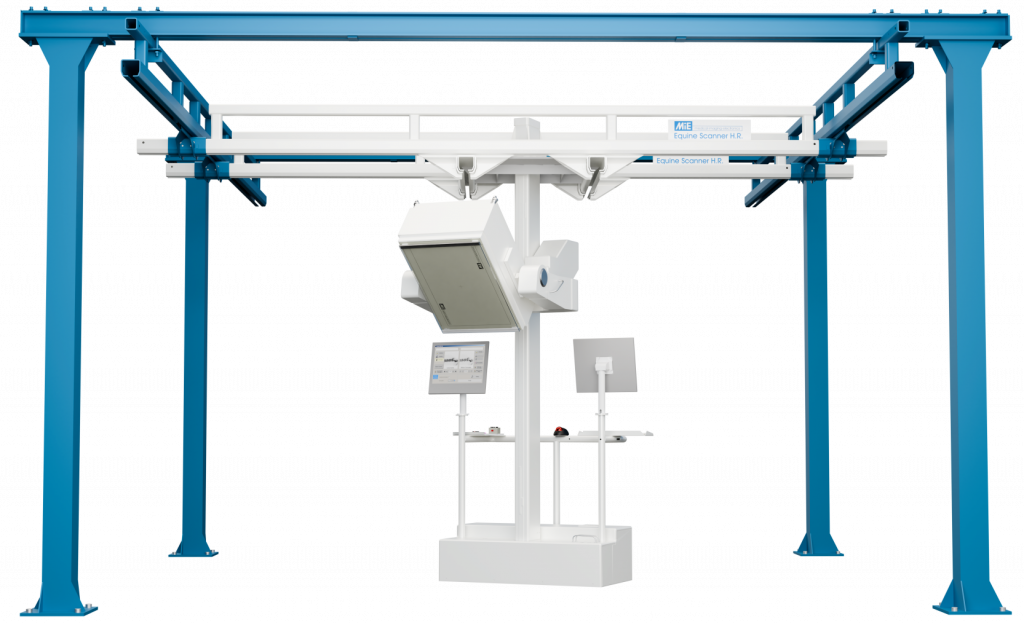

Equine Scanner H.R. 2.0

It is compact, robust, and mechanically superior to pendulum suspension systems. The detector support column is mounted approximately one centimeter above the floor, allowing quick and easy movements along any axis of the gantry support. Thus, the gantry operates at a low noise level.